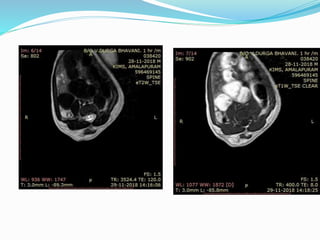

Meningocele.

A and B, Sagittal (A) and axial (B) T2-

weighted MR

images in 6-month-old boy show small

anterior

meningocele (arrows